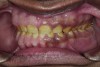

Figure 6. Preoperative maxillary occlusal view.

Figure 6

Figure 7. Preoperative mandibular occlusal view.

Figure 7

A thorough clinical examination and analysis were carried out to assess the esthetic and functional problems of the patient (Figure 2 through Figure 7). The medical history was non-contributory, except for mild leukoderma. Temporomandibular joint (TMJ) function was within normal range.